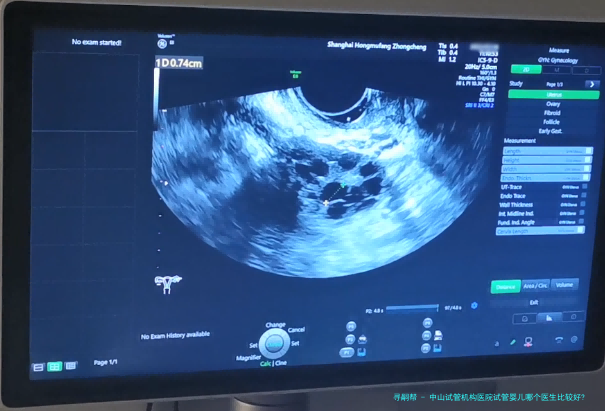

中山试管婴儿机构医院的试管婴儿移植过程严格遵循规范,旨在最大程度地提升成功率。具体过程如下:

胚胎培养:将促排卵后的卵子和精子在实验室进行受精和培养,待胚胎发育到5-8个细胞期后进行移植评估。 宫颈检查:使用超声刀对宫颈进行观察和检查,确保宫颈健康状况良好。 胚胎移植:将优质胚胎经阴道或子宫腔内种植到女性子宫内。 移植后恢复期:患者需保持充分休息,避免剧烈运动和性生活,并接受药物治疗以提高妊娠成功率。中山试管机构医院凭仗雄厚的医疗力量、先进设备和专业的医护团体,专心于为每一位病患提供优质的试管婴儿服务。要是您正进行考虑寻求试管婴儿治疗,建议您咨询中山试管机构医院相关专业人士,取得更详细的信息和个性化的方案。